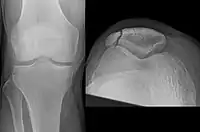

Comminuted fracture of patella

Osteochondral fracture of patella